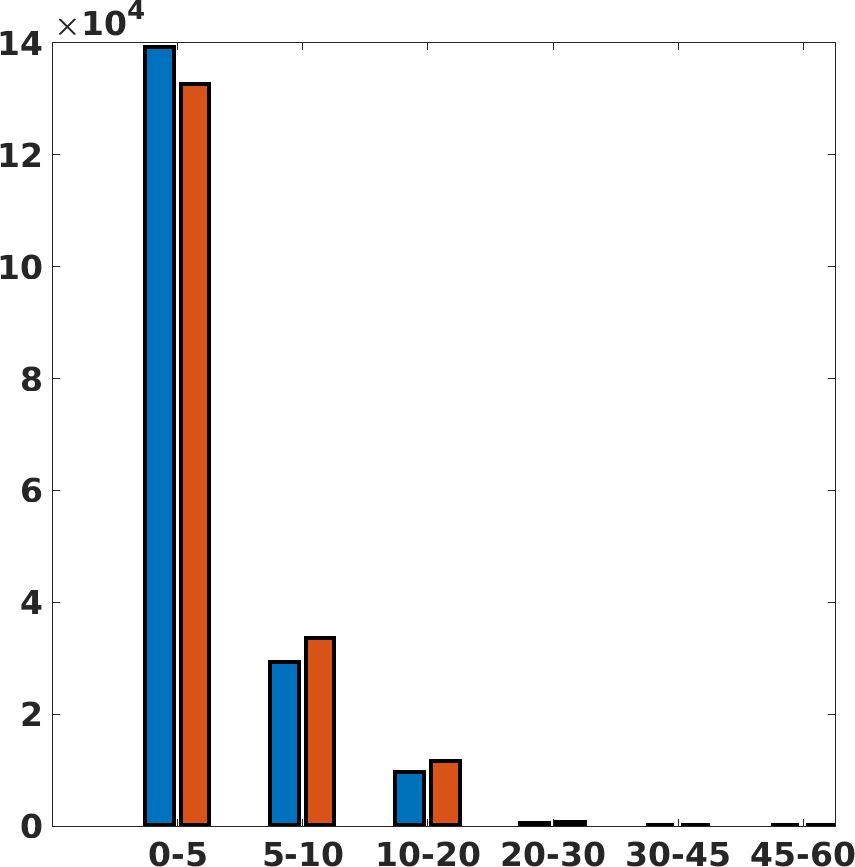

Fig. 7(a-b-c, right) shows the histogram of the absolute value of the error with respect to the target image, of the prediction and Cubic convolution results, respectively. The histograms show the number of pixels where the prediction error is lower than 5 (i.e., the first bin of the histogram), which means very similar to the target when visually analysing the images. From the Cubic convolution to the predicted images, this value increases of on obstetric 4X raw images, on cardiac 4X raw images, and on abdominal 4X raw images.

Fig. 17 (left) shows the box plot of the quantitative metrics, comparing the target images with the prediction and the Cubic convolution, respectively. The PSNR metric is computed on a data set of 200 images, belonging to the same district, and with the same up-sampling factor. Analysing the obstetric anatomical district and concerning the corresponding raw images (Fig. 7 (a, left)), the denoising allows the network to significantly improve the results of the up-sampling and the prediction. In particular, comparing the target images with the predicted images, the median PSNR value of obstetric 2X denoised images is 51.8, compared to the median PSNR value of obstetric 2X raw images which is 36.9.

Fig. 17 (right) shows the histogram of the absolute value of the error with respect to the target, of the prediction and Cubic convolution respectively. This result shows that our framework increase of and (2X and 4X, respectively) the number of pixels where the prediction error is lower than 5, which is very similar to the target when visually analysing the images, and improved with respect to the learning framework applied to raw images. According to Fig. 18, our method improves the accuracy of Cubic convolution. For example, the SSIM increases of on cardiac 2X and the MAE increases of on abdominal 4X.